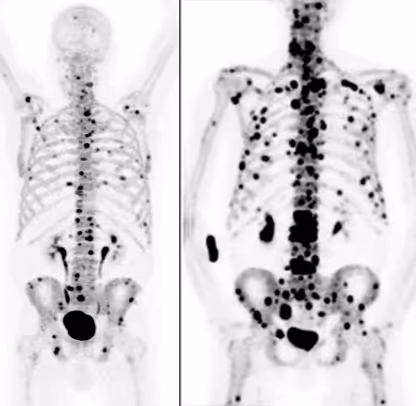

Der Nachweis erfolgt durch eine PSMA PET/CT . Diese spezielle nuklearmedizinische Untersuchung zeigt, ob und in welchem Ausmaß die Tumorherde PSMA aufnehmen. Gleichzeitig wird sichtbar, wo sich aktive Metastasen im Körper befinden.

Nur wenn die Bildgebung eine deutliche PSMA-Anreicherung in den Tumorherden zeigt, gilt die Therapie als biologisch geeignet. Fehlt diese Ausprägung oder ist sie nur sehr gering, ist die Wirksamkeit der Behandlung eingeschränkt oder nicht zu erwarten.

Die PSMA PET/CT ist daher kein ergänzender Baustein, sondern eine grundlegende Voraussetzung der Indikationsprüfung. Sie stellt sicher, dass die Therapie nur dann eingesetzt wird, wenn eine realistische Wirkung möglich ist.